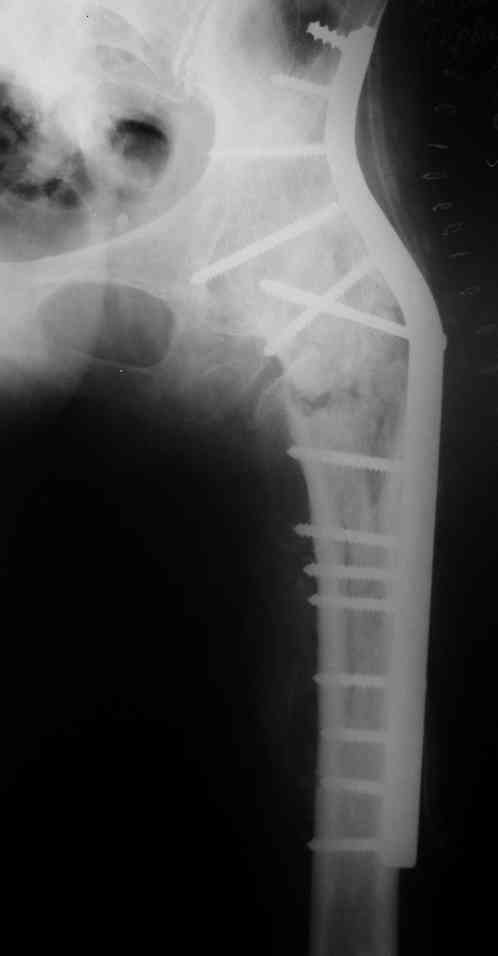

Re: перелом бедра+анкилоз тазобедренного сустава

Спасибо за совет и комментарии. Выбор остановили на длинной пластине DCP. Нам показалось, что в нашей ситуации так будет прочнее, по сравнению с клинковой пластиной или DHS.